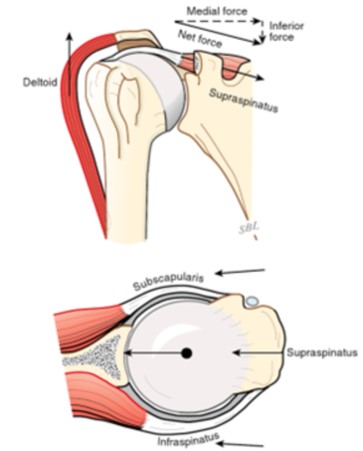

Az ép rotátorköpeny egyik fő feladata, hogy a felkarcsont fejét az ízületi tányér közepén tartja. Nagyméretű, régóta fennálló rotátorköpeny szakadás ezt az egyensúlyi helyzetet megzavarja és a humerus fej decentralizáltá válik. A rotátorköpeny funkciójának elvesztése lehetővé teszi, hogy a deltoid izom felfelé húzza a felkarcsont fejét, ami hosszú távon az ízület kopásához vezet.